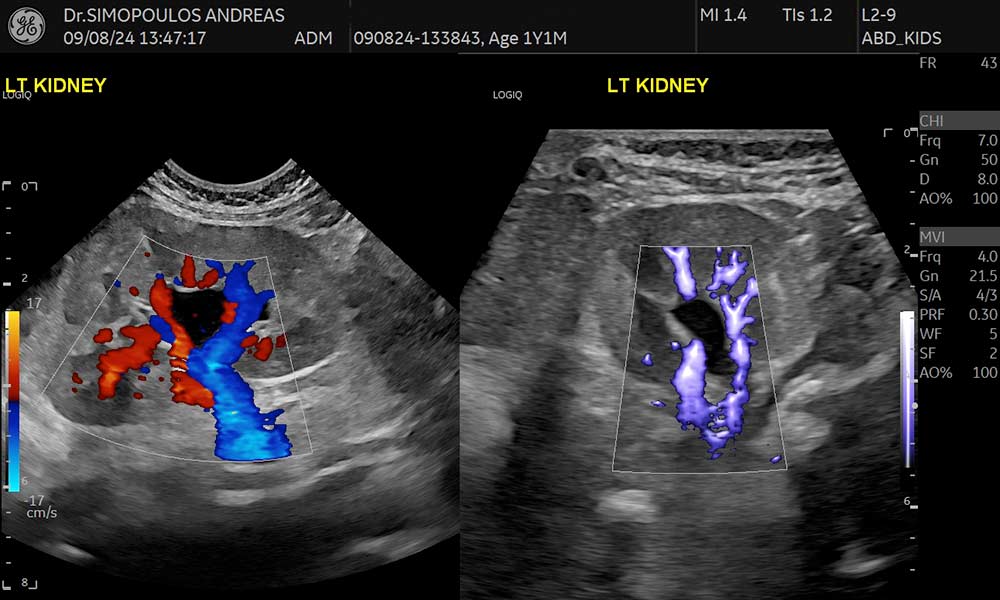

Εκτός από τις κλασικές μεθόδους (Color Doppler και Power Doppler), υπάρχει η δυνατότητα για πιο αντικειμενική τεχνική ανίχνευση της μικροαγγείωσης – MVI (Microvascular Imaging), τεχνική B-Flow, σε περιοχές ιδιαίτερα χαμηλών αιμοδυναμικών ροών καθώς και η νέα τεχνολογία Radiant Flow (Εξελιγμένη απεικόνιση έγχρωμου Doppler η οποία προσφέρει πληροφορία βάθους για την καλύτερη οριοθέτηση των αγγείων προσδίδοντας την αίσθηση της 3D απεικόνισης).